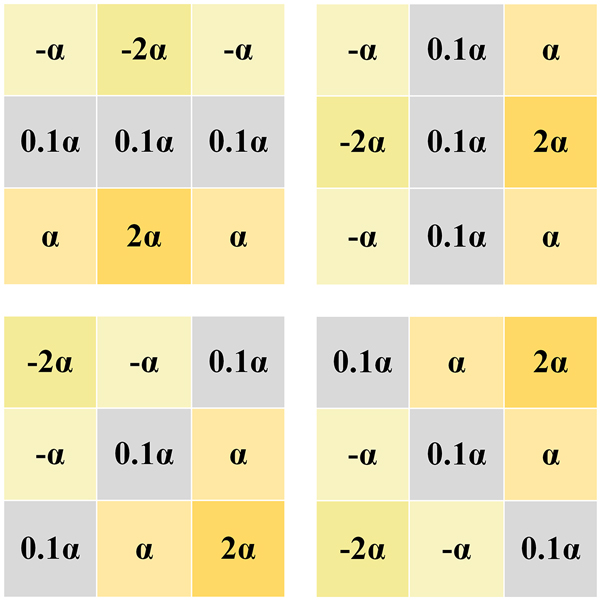

Sobel convolution block

In order to enrich the input information of the model, a trainable sobel convolution block is used as the edge enhancement module of the network, and some changes are made to it while retaining the excellent edge extraction ability of the sobel operator, as shown in Figure 3.

Learnable sobel operator.

When processing LDCT images, it is found that the edge information extracted by using a single traditional sobel operator is incomplete. In this case, the absence of contour information is more serious. Different from the traditional fixed-valued Sobel operator [28], EDCNN [15] proposes a trainable Sobel operator, which defines four operators in the horizontal, vertical and diagonal directions as a group, and this module is also used in DEformer [29], so that the parameter values can be adaptively adjusted during the optimization training process to extract the edge information with different intensities. In order to make the CECDM model extract edge information more accurately, we make some modifications on this basis by changing the learnable parameter α in the sobel algorithm from 0 to 0.1, and other parameters remain unchanged.